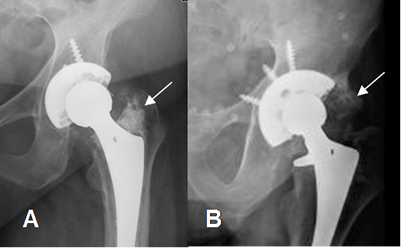

Fig 126 A. Osificación heterotópica.

A: y B: Rx AP. Calcificación anormal por encima del trocánter mayor y sobre el trocánter menor en A y por debajo del acetábulo en B, por osificación heterotópica.

Adicionalmente en A, hay aumento del ángulo de inclinación de la prótesis, que después se luxó.